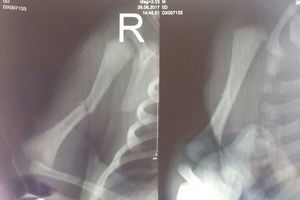

fracture of humerus in the newborn